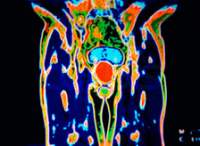

Tumore alla prostata : arriva un nuovo farmaco. Il professor Giuseppe Procopio dell’Istituto dei tumori: Aumenta la capacità di controllo del cancro e migliora l. UN nuovo farmaco per il tumore della prostata resistente alla castrazione può ridurre il rischio di comparsa delle metastasi del e migliorare la sopravvivenza, con una riduzione del del rischio di morte. Tuttavia, in quasi tutti i casi, dopo un certo periodo di tempo il cancro diventa resistente alla terapia ormonale convenzionale e può diffondersi in altre parti del corpo.

L’approvazione del nuovo farmaco segna una nuova importante opzione per la comunità medica che si occupa di curare questo tipo di cancro. Una svolta sembra essere arrivata nella lotta al cancro alla prostata.